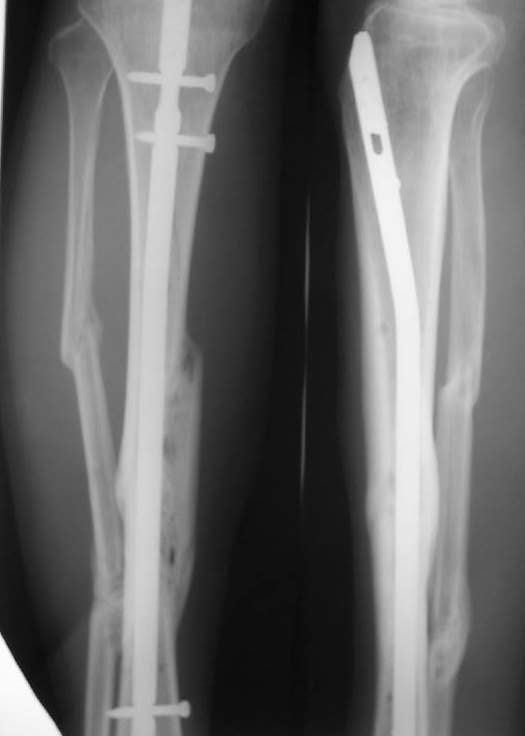

Re: Неправильно сросшийся перелом голени

У нас, наверно, была бы сделана чрескожная остеотомия малоберцовой кости, формирование и рассверливание канала большеберцовой, закрытая остеоклазия, и закрытое же штифтование. За счет устранения варуса дефицит длины уменьшится. Можно и подтянуть дистрактором одномоментно.

При невозможности или чрезмерной травматичности одномоментного восстановления длины можно пойти двухэтапно (аппарат, потом гвоздь). Похожий пример см. тут. Прошло уже года полтора после остеосинтеза. Может, коллега Зырянов покажет годичный результат, если есть?

Александр Николаевич, к сожалению больной не является на контрольные осмотры. Я последний раз видел больного, когда прошло 7 месяцев после операции БОС. У него все хорошо. Каких либо жалоб и ограничений в нагрузке нет. Высылаю снимки до операции и последние снимки.